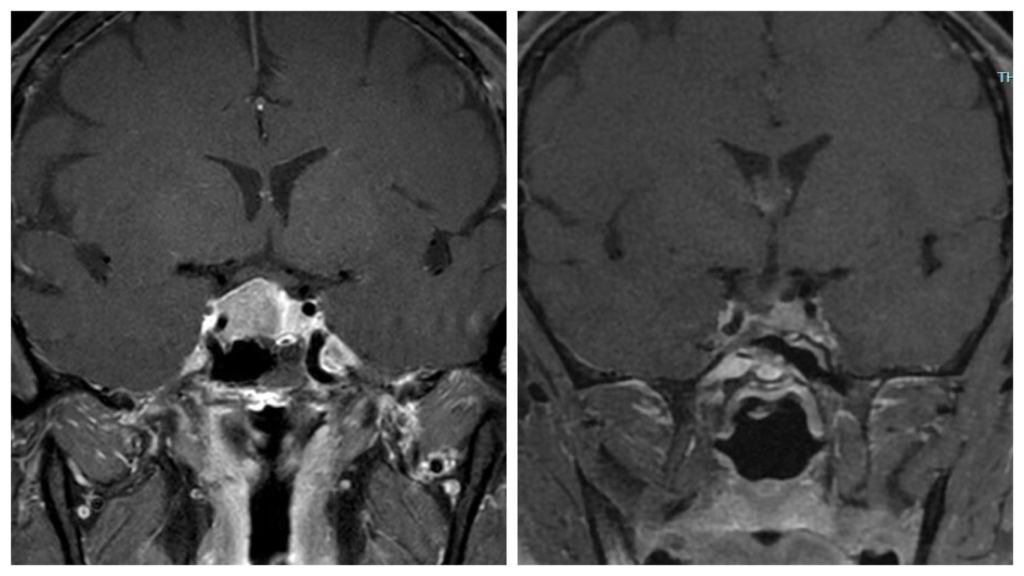

นอกจากผู้ป่วยรายนี้จะมีอายุน้อยและความดันโลหิตสูงมากแล้ว ยังพบว่ามีน้ำหนักเพิ่มขึ้นอย่างรวดเร็ว (50 ไปเป็น 67 กิโลกรัม)ร่วมกับมีลักษณะ “บวม” บริเวณกลางตัวซึ่งเป็นลักษณะเฉพาะที่ทำให้คิดถึง “โรคคุชชิง”(Cushing’s disease) เมื่อนำผู้ป่วยไปผ่านการตรวจทางห้องปฏิบัติการ (ซึ่งมีขั้นตอนมากมายดังที่หมอเคยกล่าวไปในตอนก่อนแล้ว) ก็ยืนยันว่าเป็นโรคนี้จริงร่วมกับการทำ MRI พบเนื้องอกต่อมใต้สมองที่เป็นสาเหตุดังภาพด้านล่าง